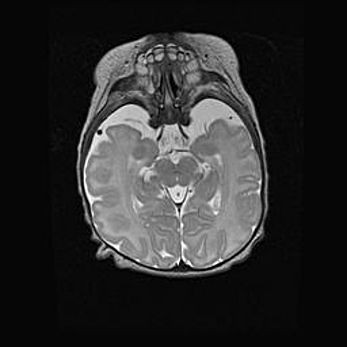

Церебральная ишемия II.

Возраст: 5 дней

Вес: 3400 г

Пол: женский

Окружность головы: 35 см

Срок гестации: 39 недель

Церебральная ишемия – это заболевание, характеризующееся недостаточностью (гипоксией) либо полным прекращением (аноксией) снабжения мозга кислородом по причине закупорки одного или нескольких сосудов. Это приводит к  что метаболическим расстройствам различной степени тяжести в тканях головного мозга, развитию коагуляционных некрозов и гибели нейронов.